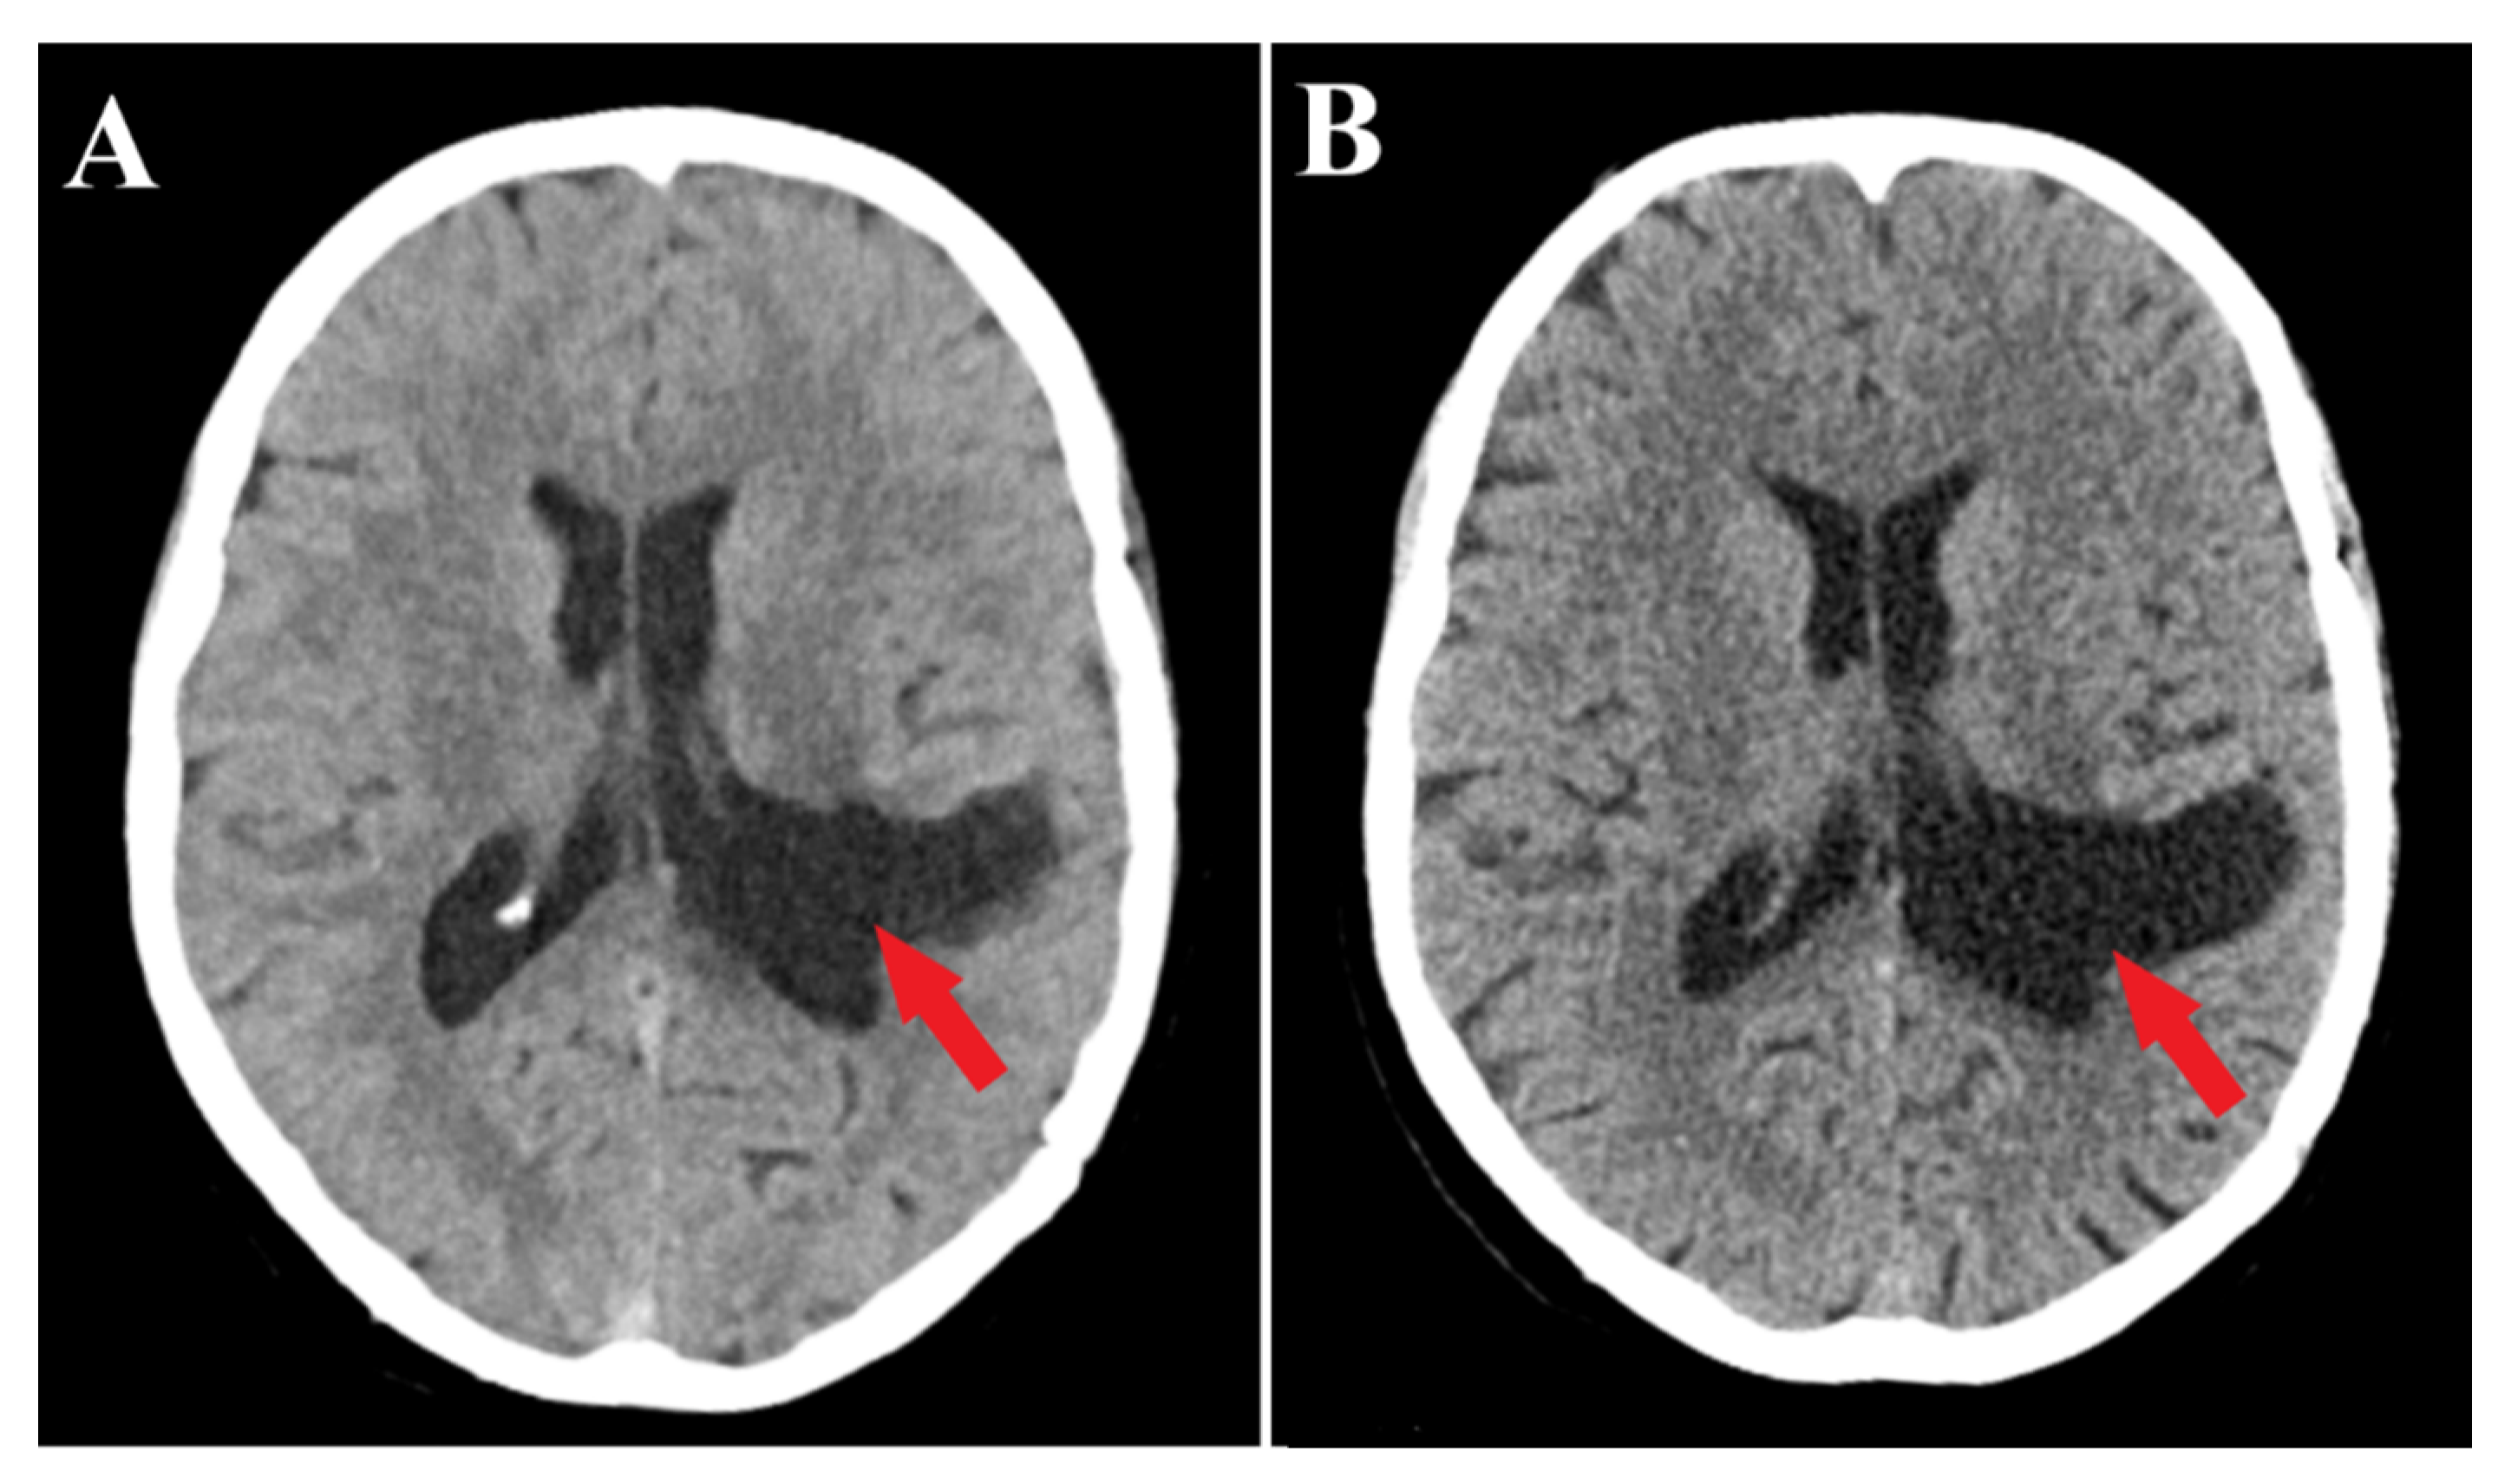

Follow-up evaluations at 3 months and 1 year post-surgery revealed mild, predominantly expressive mixed aphasia. Non-contrast CT scans identified a region of hypodensity in the left temporo-parietal area, indicative of post-surgical changes without any mass effect or contrast uptake, suggesting a sequela. No evidence of tumor recurrence or residual meningioma was observed (Figure 5). Throughout the follow-up period, the patient was maintained on antiepileptic medication, with no reported episodes of seizures.

Figure 5.

Follow-up CT scans. 3 months follow-up CT scan (A) and 1 year follow-up CT scan (B) demonstrate successful complete resection of the meningioma (red arrows) without residual tumor fragments.